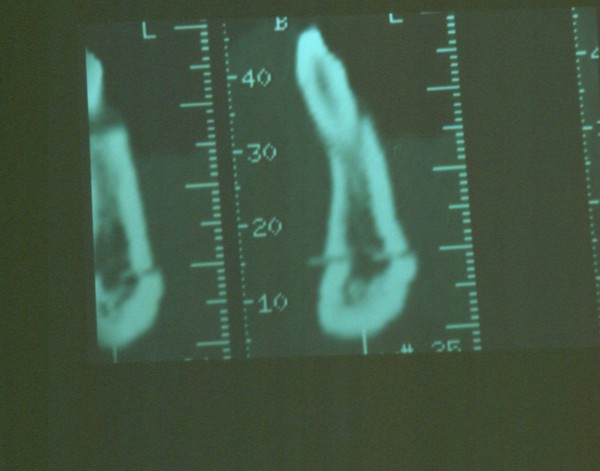

Instalamos en su interior una galga de profundidad, ingresando esta en su totalidad.(DIAPO 5-6)

DIAPO 6

Hubiera sido necesaria la comparación osteodensitométrica entre la zona a implantar y otras zonas maxilares.(DIAPO 8-9-10)

DENSIDAD PROMEDIO:194.87 DENSIDAD PROMEDIO:158.49

DIAPO 8 DIAPO 9

DENSIDAD PROMEDIO:168.5